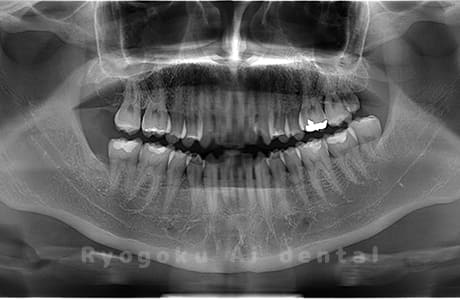

真っ直ぐ生えている親知らず

親知らずが真っ直ぐ生えているタイプです。

このタイプは真っ直ぐ生えていて咬み合わせに問題がなければ、抜歯しないケースもあります。ただし、虫歯になっていたり、痛みがあったり、咬み合わせが悪かったりすると抜歯をおすすめします。